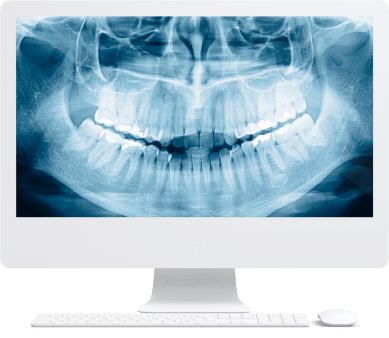

По уникальной методике

БЕЗ отёков и надрезов